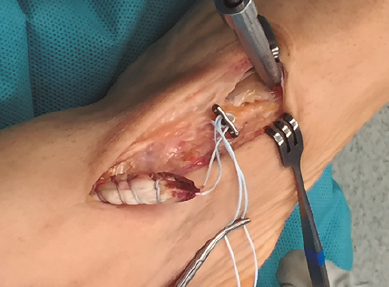

Figura 4. Preparación de túnel óseo en cuña medial con broca de 4,5 mm y colocación de los hilos en la placa metálica de 4 × 12 mm.

Se realiza túnel con broca de 4,5 mm al nivel de la cortical dorsal de la cuña medial con oblicuidad de proximal a distal hasta llegar a la cortical plantar (Figura 4). Posteriormente, se ensancha el mismo al nivel de la primera cortical según el diámetro del tendón tibial anterior, utilizando una pinza gubia o un avellanador.